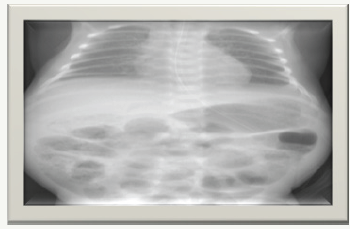

k) On day 7 of life, he was noted to have abdominal distension that was rapidly progressive to a shiny red abdomen with increased gastric aspirates (Figure 2 & 3).

Figure 2:

Figure 3: